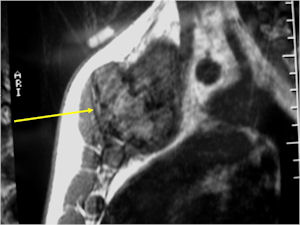

CT Scan:

- More useful for detecting mineralization and evaluating extent of bone destruction than plain X-ray

MRI:

- Also useful in determining extent

- There is often extensive edema around the tumor in the surrounding bone and soft tissues that can lead to a misdiagnosis of a malignant tumor.